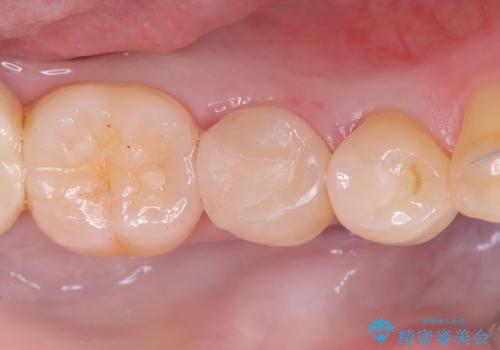

セラミックインレーによる虫歯治療

- 右下5の虫歯をセラミックインレーで修復しました。虫歯は進行することで歯に悪影響を及ぼし、放置するとさらなる問題を引き起こす可能性があります。再発のリスクをできるだけ回避するため、セラミックインレーを用いて治療を行いました。

装着する際にはラバーダムを使用しています。